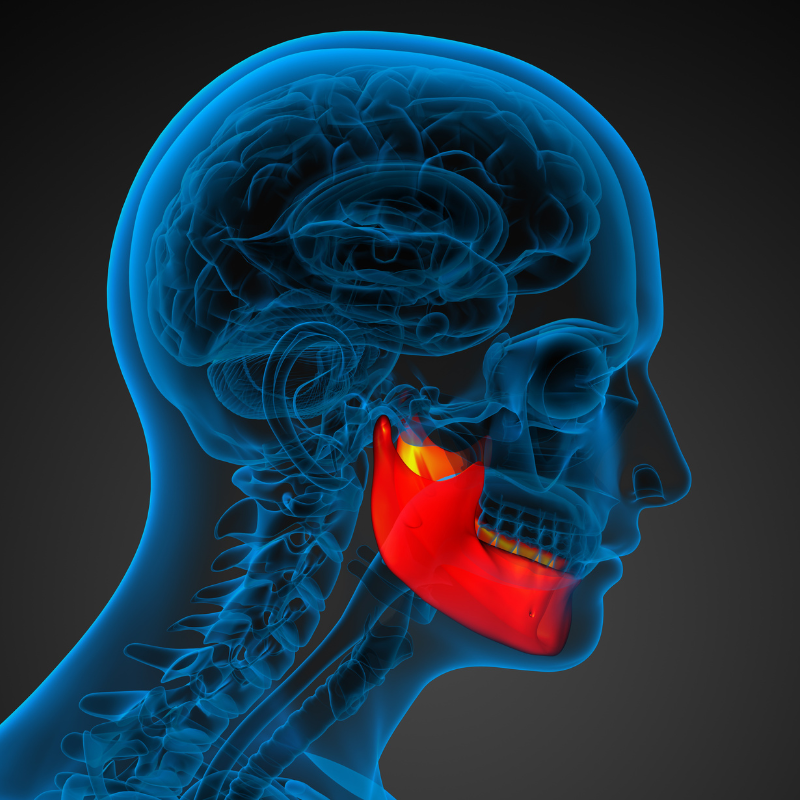

Fractures (broken bones) can involve the upper jaw, lower jaw , cheekbones, eye socket, and combinations of these bones. Treatments for these injuries are frequently managed under general anaesthesia by maxillofacial surgeon.

Whether the result of an accident or sports-related injury of the face or mouth, trauma can significantly change your appearance and can make breathing and eating difficult. Dr. V.Suresh is an expert in treating facial fractures and can repair most of these injuries through the mouth, eliminating visible scars.